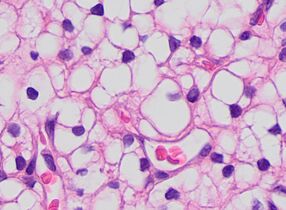

The most commonly used stain in histology is a combination of hematoxylin and eosin (often abbreviated H&E). Hematoxylin is used to stain nuclei blue, while eosin stains the cytoplasm and the extracellular connective tissue matrix of most cells pink. There are hundreds of various other techniques which have been used to selectively stain cells. Other compounds used to color tissue sections include safranin, Oil Red O, congo red, silver salts and artificial dyes. Histochemistry refers to the science of using chemical reactions between laboratory chemicals and components within tissue. A commonly performed histochemical technique is the Perls' Prussian blue reaction, used to demonstrate iron deposits in diseases like Hemochromatosis.[2]

Pleomorphic when having different sizes and shapes. This often correlates with an increased nucleus to cytoplasm ratio. These features generally indicate malignancy.